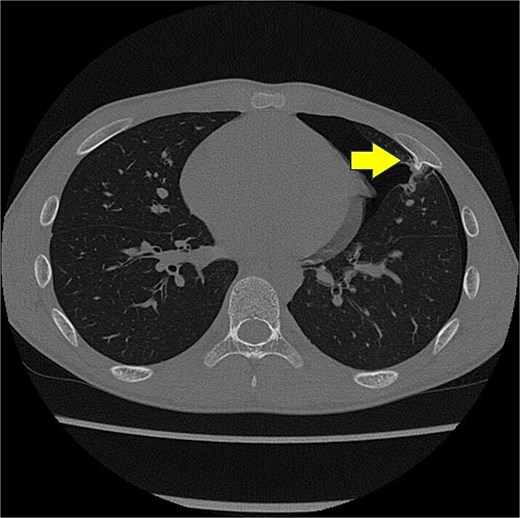

A 13-year-old boy presented with chest pain and dyspnea. There was no significant medical or family history. Chest radiography showed a left pneumothorax and opacity in the left middle lung field (Fig. 1). Computed tomography (CT) showed a left pneumothorax and a bony, pedunculated mass arising from the fifth rib. The cortical bone and bone marrow continued to move away from the fifth rib (Fig. 2). The mass was slim, pedunculated, and pointed directly inward to the thoracic cavity (Fig. 3), and it was suspected to have invaded the left upper lobe of the lung. There were no bullae, and the patient had no history of trauma. The patient was diagnosed with pneumothorax due to a costal osteochondroma. The patient was admitted to our hospital and underwent surgery to remove the costal osteochondroma and treat the left pneumothorax. Three-port video-assisted thoracic surgery revealed no bullae but a bony and pedunculated osteochondroma arising from the anterior aspect of the fifth rib (Fig. 4). There was a wound in the left lingular segment and a thickened visceral pleura around the wound (Fig. 5). We performed wedge resection of the lingular segment, including the wound and thickened visceral pleura. We removed the osteochondroma during thoracoscopic surgery without partial rib resection using electrocautery and Cooper scissors. A water-sealing test revealed no air leakage.

Three-dimensional computed tomography. Slim and pedunculated osteochondroma arising from the anterior fifth rib into the thoracic cavity.

Surgical resection of osteochondromas is recommended when they emerge after puberty, become symptomatic, exhibit rapid growth, or show signs of malignant transformation [4, 7]. Complete resection by removing the osteochondroma at the normal bone base, with consequent removal of the cartilage cap and perichondrium, is recommended [1]. In the absence of remnants of the cartilage cap or perichondrium, the risk of relapse is extremely low [1]. Costal osteochondromas are resected with or without partial rib resection via thoracotomy or thoracoscopic surgery, depending on the case [2–9]. Fujita et al. reported that surgical resection via thoracoscopic surgery was effective for slim and pedunculated costal osteochondromas [8]. Three-dimensional CT can clearly describe the morphology and extent of osteochondromas. Thoracoscopy is useful for confirming the location, morphology, and extent of osteochondromas [4]. This may help in determining the surgical approach and procedure. In the present case, the costal osteochondroma was slim and pedunculated in the three-dimensional CT and thoracoscopy. These findings helped us continue and complete the resection of the costal osteochondroma via thoracoscopic surgery without partial rib resection.